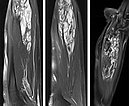

MRT-Bildgebung des Unterarms (T1 mit spektraler Fettsättigung nach Gadoliniumgabe). Sie demonstriert jetzt einen fast vollständigen Verschluss der dysplastischen Venen, die im Verlauf nach Sklerosierung initial thrombosiert und im Weiteren dann vernarbt sind.